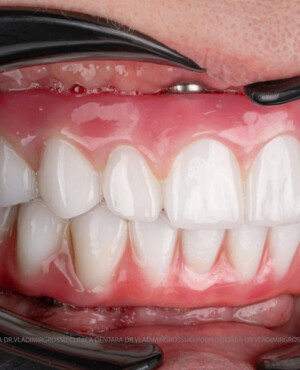

Caz 1

Caz 2